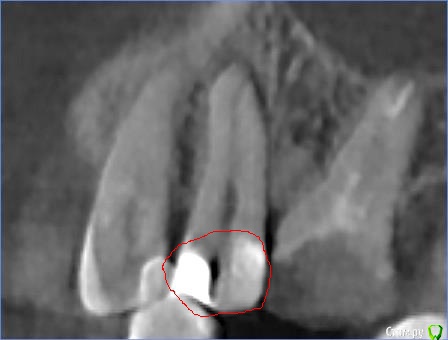

Faramir Опубликовано 30 апреля, 2019 Поделиться Опубликовано 30 апреля, 2019 (изменено) Посетил клинику в которой врач (причем главный) диагностировал кариес между 1.5 со стороны 1.4. На зубе уже была другая пломба со стороны 1.6. Через несколько месяцев я сделал КТ для консультаций по имплантации и рассматривая этот зуб заметил что под пломбой видна не маленькая полость. Обратился в клинику к врачу, после чего мне был вынесен вердикт что это "рог пульпы" и вроде как все нормально. Вопрос может ли быть рог пульпы в 1.5 зубе так высоко и прилегать непосредственно к пломбе черным пятном? Или это банальная ошибка врача который не достаточно утрамбовал материал или материал был не достаточно текуч для заполнения всей просверленной полости? Зуб слегка поднывает иногда. Во что может вылиться если зуб оставить как есть или его нужно обязательно переделать? Фото с КТ прилагаю. Изменено 30 апреля, 2019 пользователем Faramir Ссылка на комментарий

St. Опубликовано 30 апреля, 2019 Поделиться Опубликовано 30 апреля, 2019 Да, все нормально.Впринципе на любой кт присутствуют артефакты и она не предназначена для диагностики кариеса под пломбами 2 Ссылка на комментарий

DmitrySH Опубликовано 1 мая, 2019 Поделиться Опубликовано 1 мая, 2019 (изменено) КТ насколько я знаю является самым совершенным средством диагностики и контроля на сегодня. Но не для кариса под пломбами. т.к. любой пломбировочный материал дает искажение.Это не значит, что у вас там его нет или он есть. Как уже написали выше: очный осмотр и рентген будут более информативны Изменено 1 мая, 2019 пользователем DmitrySH Ссылка на комментарий